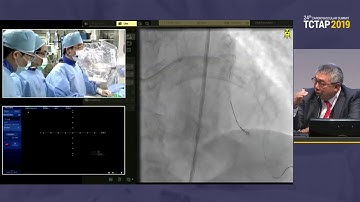

[TCTAP 2019] Master the CTO - Live Case & Lecture Session III